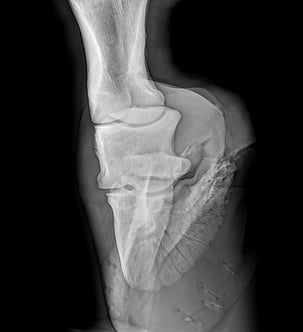

Beim 7 jährigen Wallach (Exzellente Dressurabstammung) wurde nach einem Weidegang in seinem Pensionsstall eine Lahmheit auf der rechten Vorderhand festgestellt.

Die Untersuchung in der Pferdeklinik Neugraben in Niederlenz hat die Diagnose Fissur Hufbein ergeben.

Nach zwei Wochen Boxenruhe verschlechterte sich der Zustand des Hufbeins akut. Der Wallach wurde erneut in der Pferdeklinik Neugraben untersucht und schliesslich den Bruch des Hufbeins festgestellt.